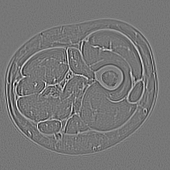

(c) LoG filtered image (σ=1.5𝜎1.5\sigma=1.5)

Obtaining local statistical measures of grayscale images may further provide a description of local texture by describing numerically the local intensity variations. In this research, both the original MRI grayscale image (Fig. 1(a)) and the outcome of a 5x5 LoG filter with σ=1.5𝜎1.5\sigma=1.5 [10] (Fig. 1(c)) are used for statistical feature extraction.

While the original grayscale image provides important differences in intensity and its variations inside tissues, the LoG filter allows for edges highlighting. Those two images are subdivided into 16x16 blocks and the mean, variance, skewness and kurtosis are computed computed inside each block.